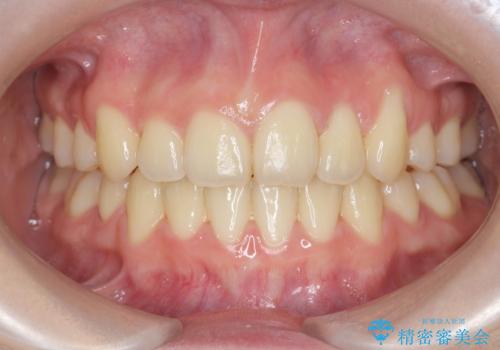

[前歯のねじれ 部分]ワイヤーとマウスピースの併用矯正治療

担当医 大元洋佑